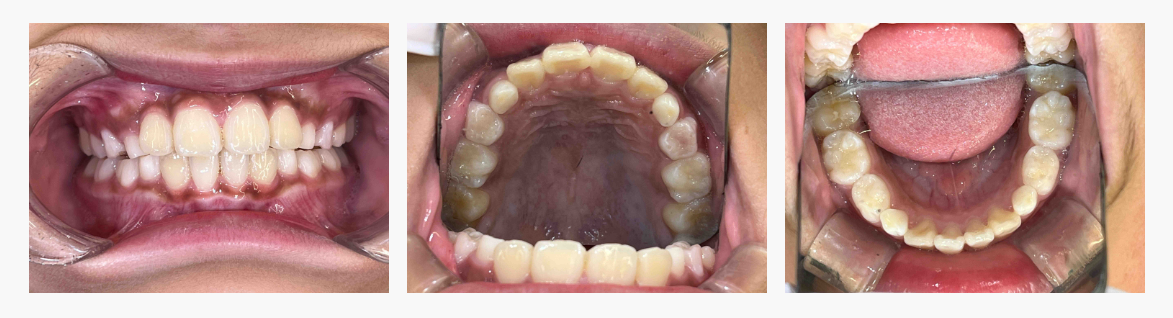

▼ After(治療後)

◆ 治療の結果

・前歯の突出感が軽減

・歯列のガタつきが改善

・口唇が自然に閉じやすくなった

歯並びと口元の機能の両面で改善がみられました。